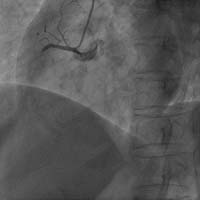

房間隔缺損封堵術